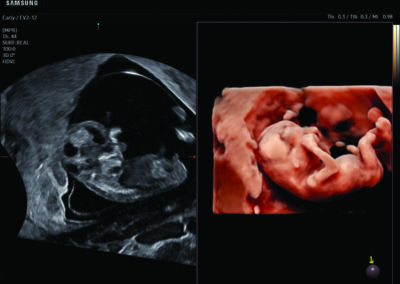

Comprehensive, advanced and expert MFM care for high-risk pregnancies